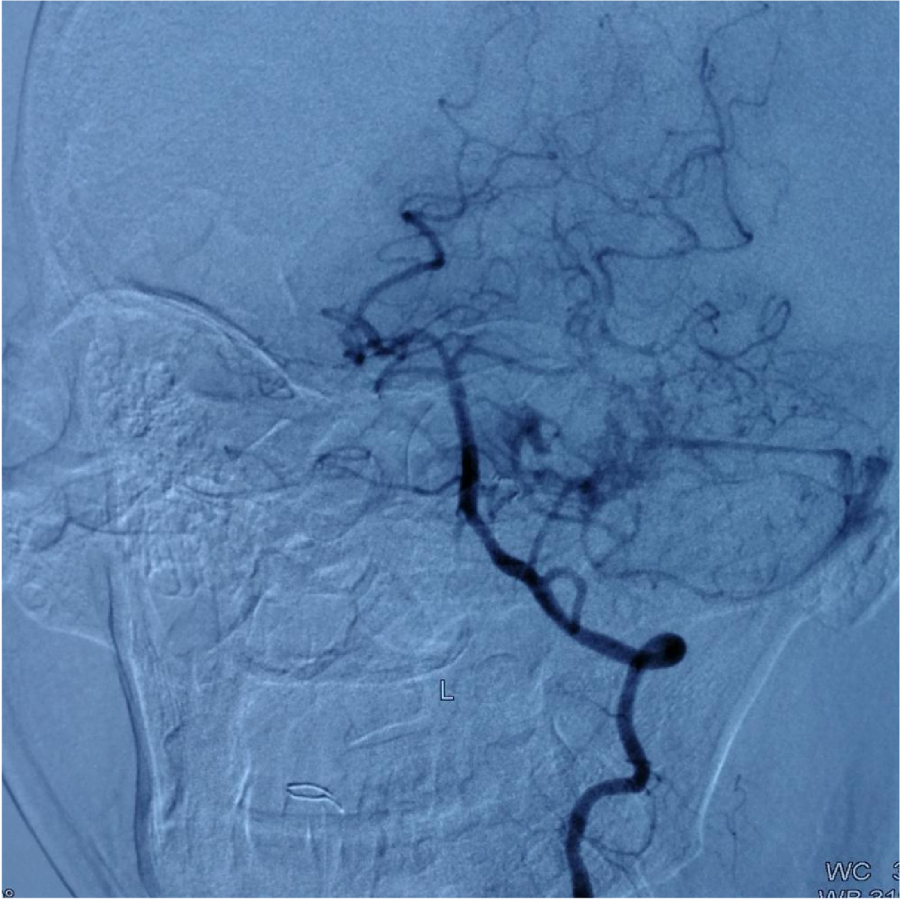

本次⼊院⾏DSA检查:PICA供⾎区有畸形⾎管团,引流到横窦

第⼀次DSA显⽰PICA供⾎

引流⾄⼄状窦

小脑后下动脉、小脑前下动脉参与供⾎

颈外动脉造影显⽰枕动脉参与供⾎